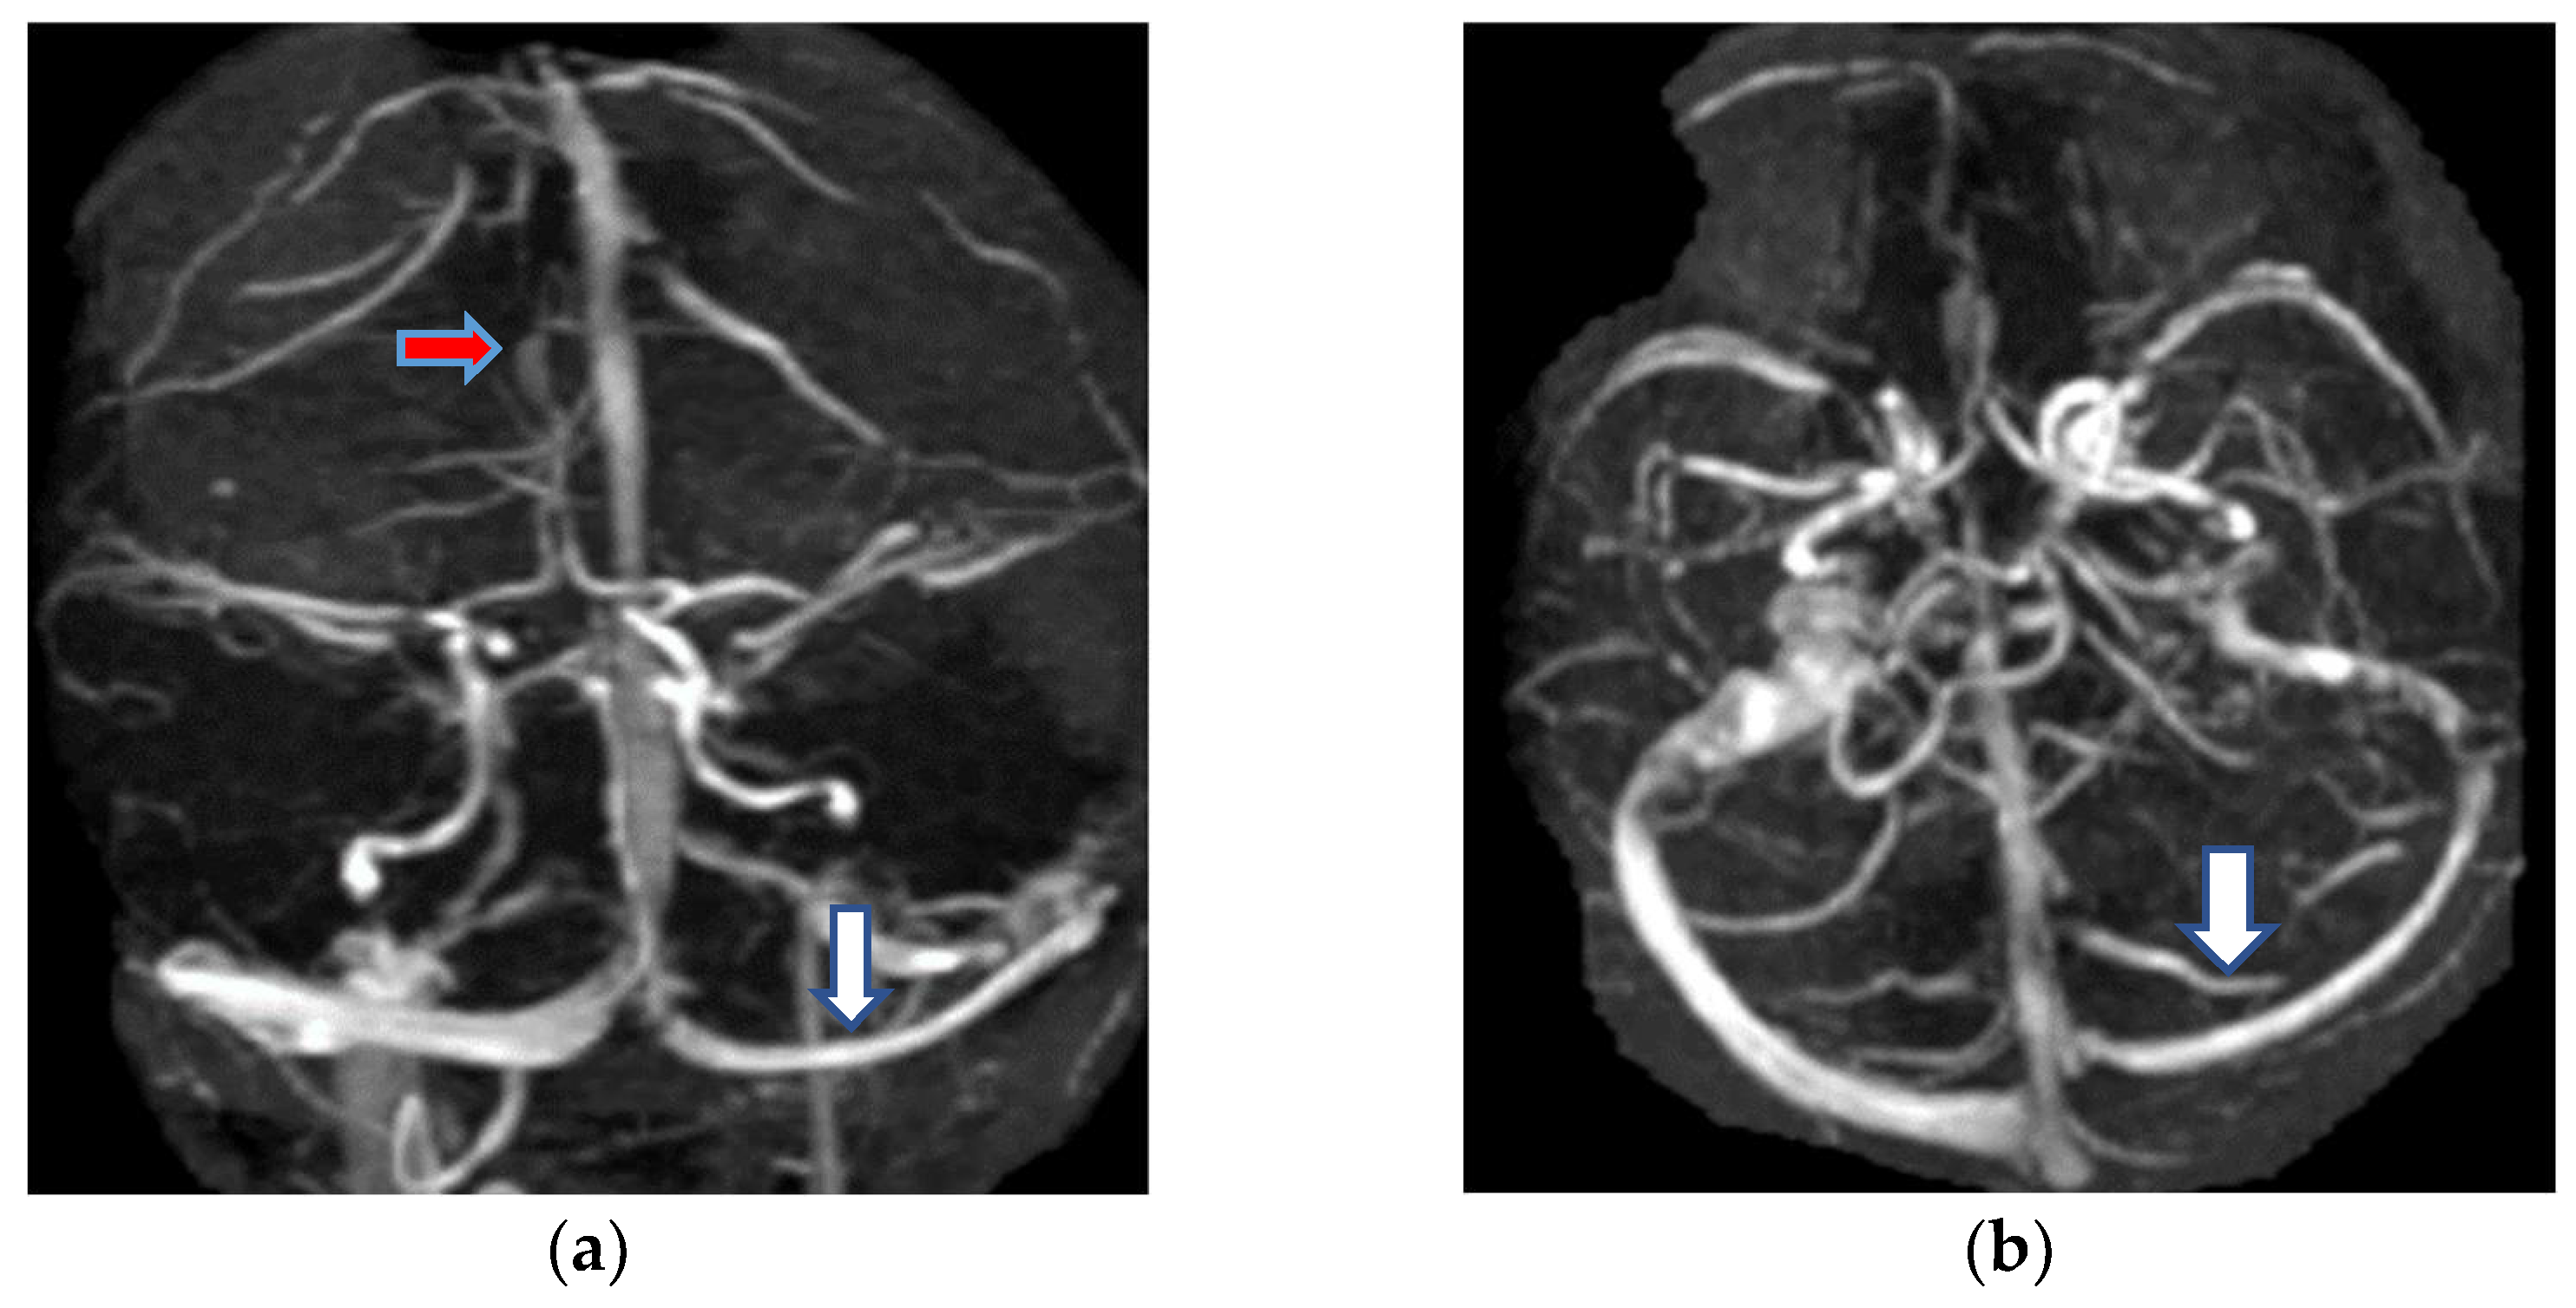

2.1.3. Neuroimaging

- Jianu, D.C.; Jianu, S.N.; Motoc, A.G.; Poenaru, M.; Petrica, L.; Vlad, A.; Ursoniu, S.; Gogu, A.E.; Dan, F.T. Diagnosis and management of a young women with isolated lateral sinus thrombosis. Rom. J. Morphol. Embryol. 2017, 58, 1515–1518. [Google Scholar] [PubMed]